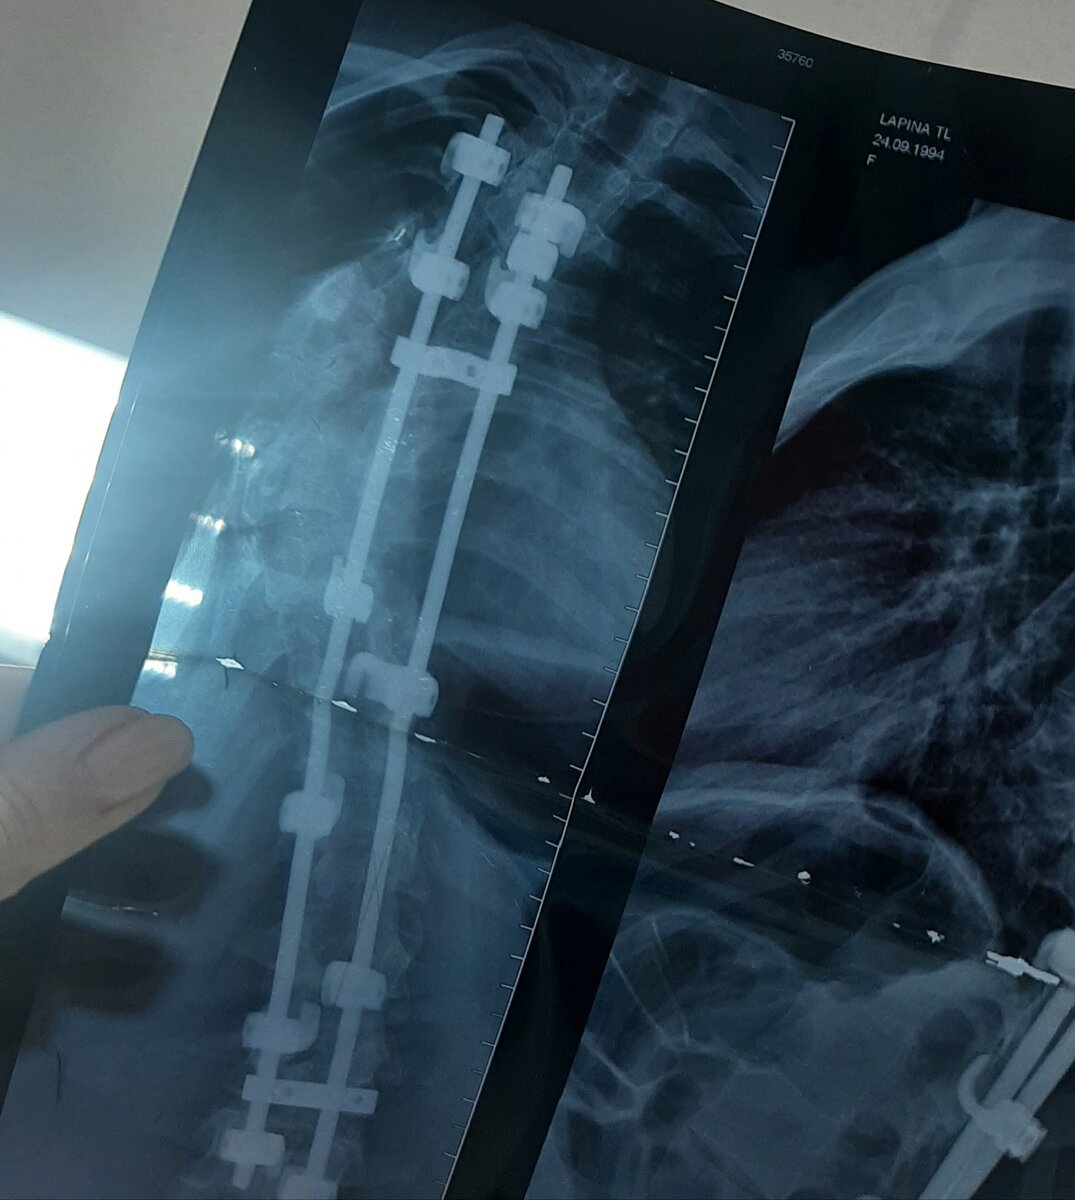

Такие конструкции ставятся на всю жизнь - их не вынимают через несколько лет, они прирастают и живут с тобой.

Вот так сейчас выглядит мой снимок